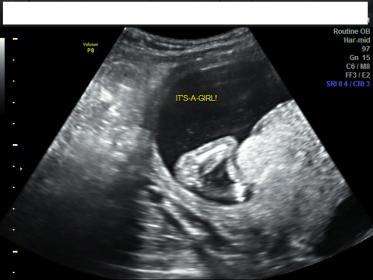

Any chance of this turning into a boy for my anatomy scan next week? :( I was 15 weeks exactly and the tech seemed pretty confident. It was done at a 2d/3d baby boutique ultrasound clinic

She said they don't guarantee until 18 weeks but that she was about 95% sure girl

I guess I'm just wondering if it looks girly to everyone else?

Yes it looks girly to me too. But the pics aren't SUPER clear. If tech says girl at 15 w - usually right.